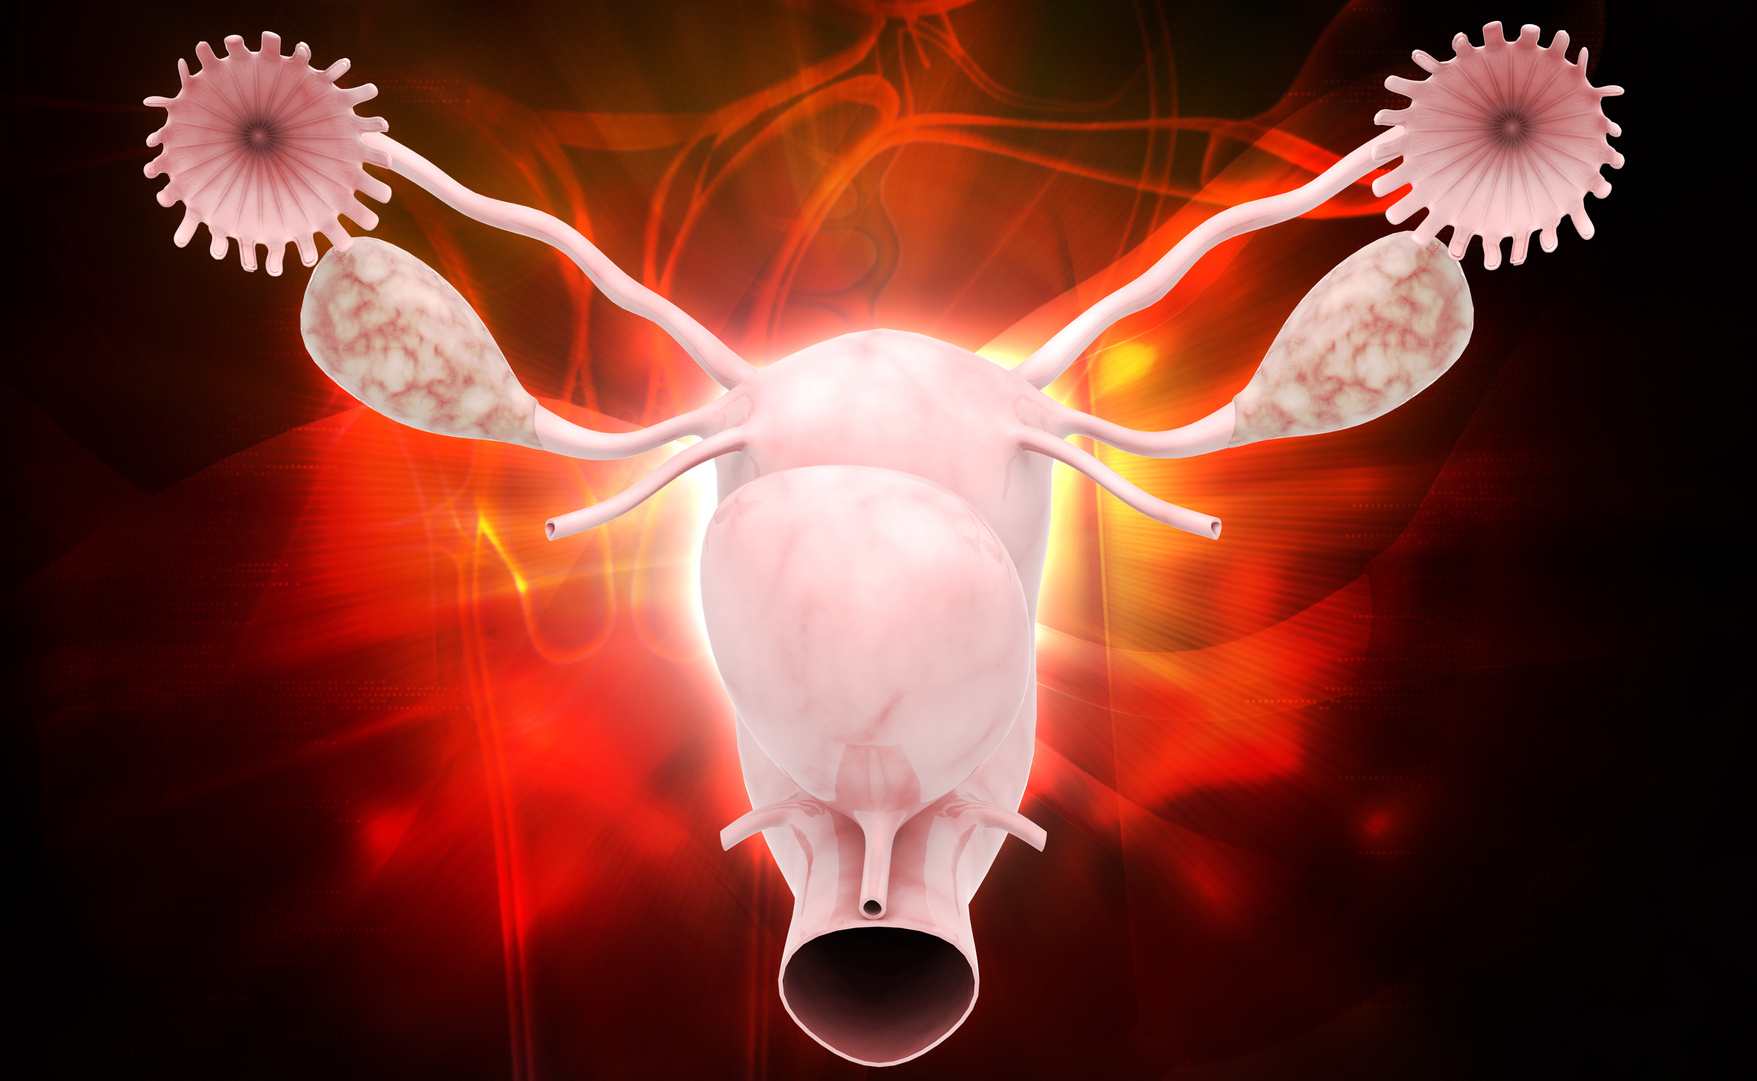

Hola, soy mama de un bebe de 15 meses q desde la semana 20 empece con contracciones de ponerse la tripa dura pero no me modificaban el cuello del utero. Por si acaso guarde reposo en cama hasta la semana 38 q me dio subida de tension y nacio por cesarea con 4 kilos y pico. Cual es q me llevo la sorpresa de q en una ecografia porque me pincho para estomular me dicen q si no me habian dicho que tengo el utero doble :-O Me dice q es dificil para quedarse embarazada, pero yo leyendo internet me he preocupado porque leo que es causa de abortos y prematuros. Entonces yo he acahacado lo de las contracciones del anterior embarazo a este utero doble, puede ser asi.? El caso es que el mes que me quede embarazada me hice una histerosaloingografia y en el informe pone utero en posicion neutras, de cavidad unica y de contornos regulares, y no ha la nada de utero doble..Me podeis tranquilizar un poco? Es q mi gine de siempre no me dijo nada de esto y no se si ya quiero quedarme embarazada otra vez cone ste problema…

Si tu útero ha sido capaz de gestar durante 38 semanas, no hay motivos para pensar que no puedas volver a gestar nuevamente. De todos modos, sería conveniente confirmar o descartar si tu útero es doble, septado o de cavidad única. En caso de tratarse de un útero septado sí que existe mayor riesgo de aborto y en caso de ser un útero doble mayor riesgo de parto prematuro.

Así que, nuestra recomendación es que acudas a tu ginecólogo para valorar qué pruebas debes realizarte. La histerosalpingografía es una prueba de alta sensibilidad pero la laparoscopia junto con una histeroscopia tiene mayor fiabilidad.